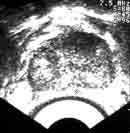

Рак предстательной железы также имеет характерные эхографические признаки. Опухолевым узлам чаще соответствуют участки пониженной эхогенности с неровным нечетким контуром (Рис. 15), причем центральная часть может иметь более интенсивный эхо-сигнал [13]. У 15-20% больных выявляются гиперэхогенные узлы (Рис. 16). Довольно часто опухолевый узел приобретает пестрый вид за счет образования гиалиновых телец, кальцинатов и участков распадающейся опухоли [11, 22].

Увеличить

Рис. 15. Трансректальные эхограммы. Рак предстательной  железы. Гипоэхогенные узлы.

Рис. 16. Трансректальная эхограмма. Рак предстательной железы. Гиперэхогенные включения.